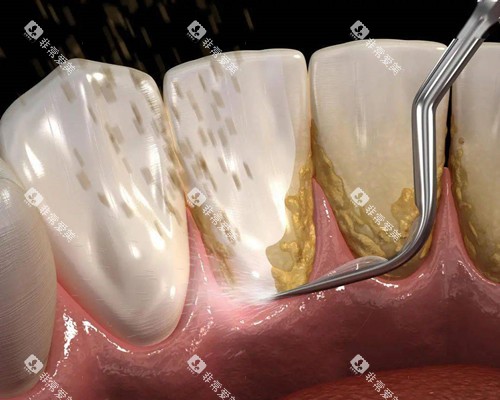

对于常见的口腔疾病,如龋齿填充、牙周炎治疗、根管治疗等,长治第二人民医院口腔科的收费都处于较为合理的水平。

以龋齿填充为例,根据填充材料的不同,价格会有所差异,但总体来说,都比市场上一些私立诊所要实惠。

而且,医生会根据患者的具体情况,为其推荐更适合的治疗方案和填充材料,在确保治疗结果的同时,尽量为患者节省费用。